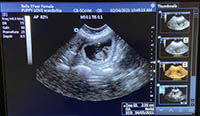

Mobile Ultrasound Pregnancy Scanning and Microchipping Services

Puppy Love scan and chip